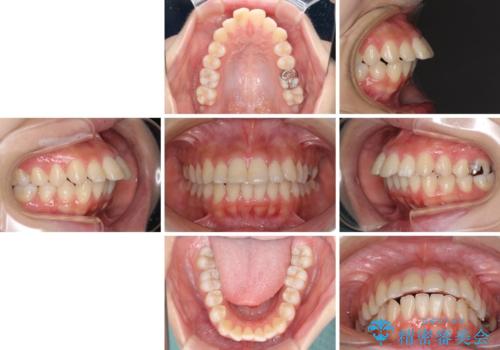

突出した口元が気になる ハーフリンガル装置による抜歯矯正

- 口元の突出感を気にして来院された患者様です。

通常では上下左右の第一小臼歯4本を抜歯しますが、下顎が左側にシフトしていたため、下顎左側のみ第二小臼歯を抜歯し、正中を合わせながら口元を下げる治療計画としました。

ハーフリンガルは、通常では表側のワイヤー矯正よりも治療期間がかかります。特に今回のように下顎左側をイレギュラーの第二小臼歯抜歯としたため、さらに時間がかかることが予想されました。

実際に治療をおこなってみると、2年を切る短期間で治療を終えることができました。